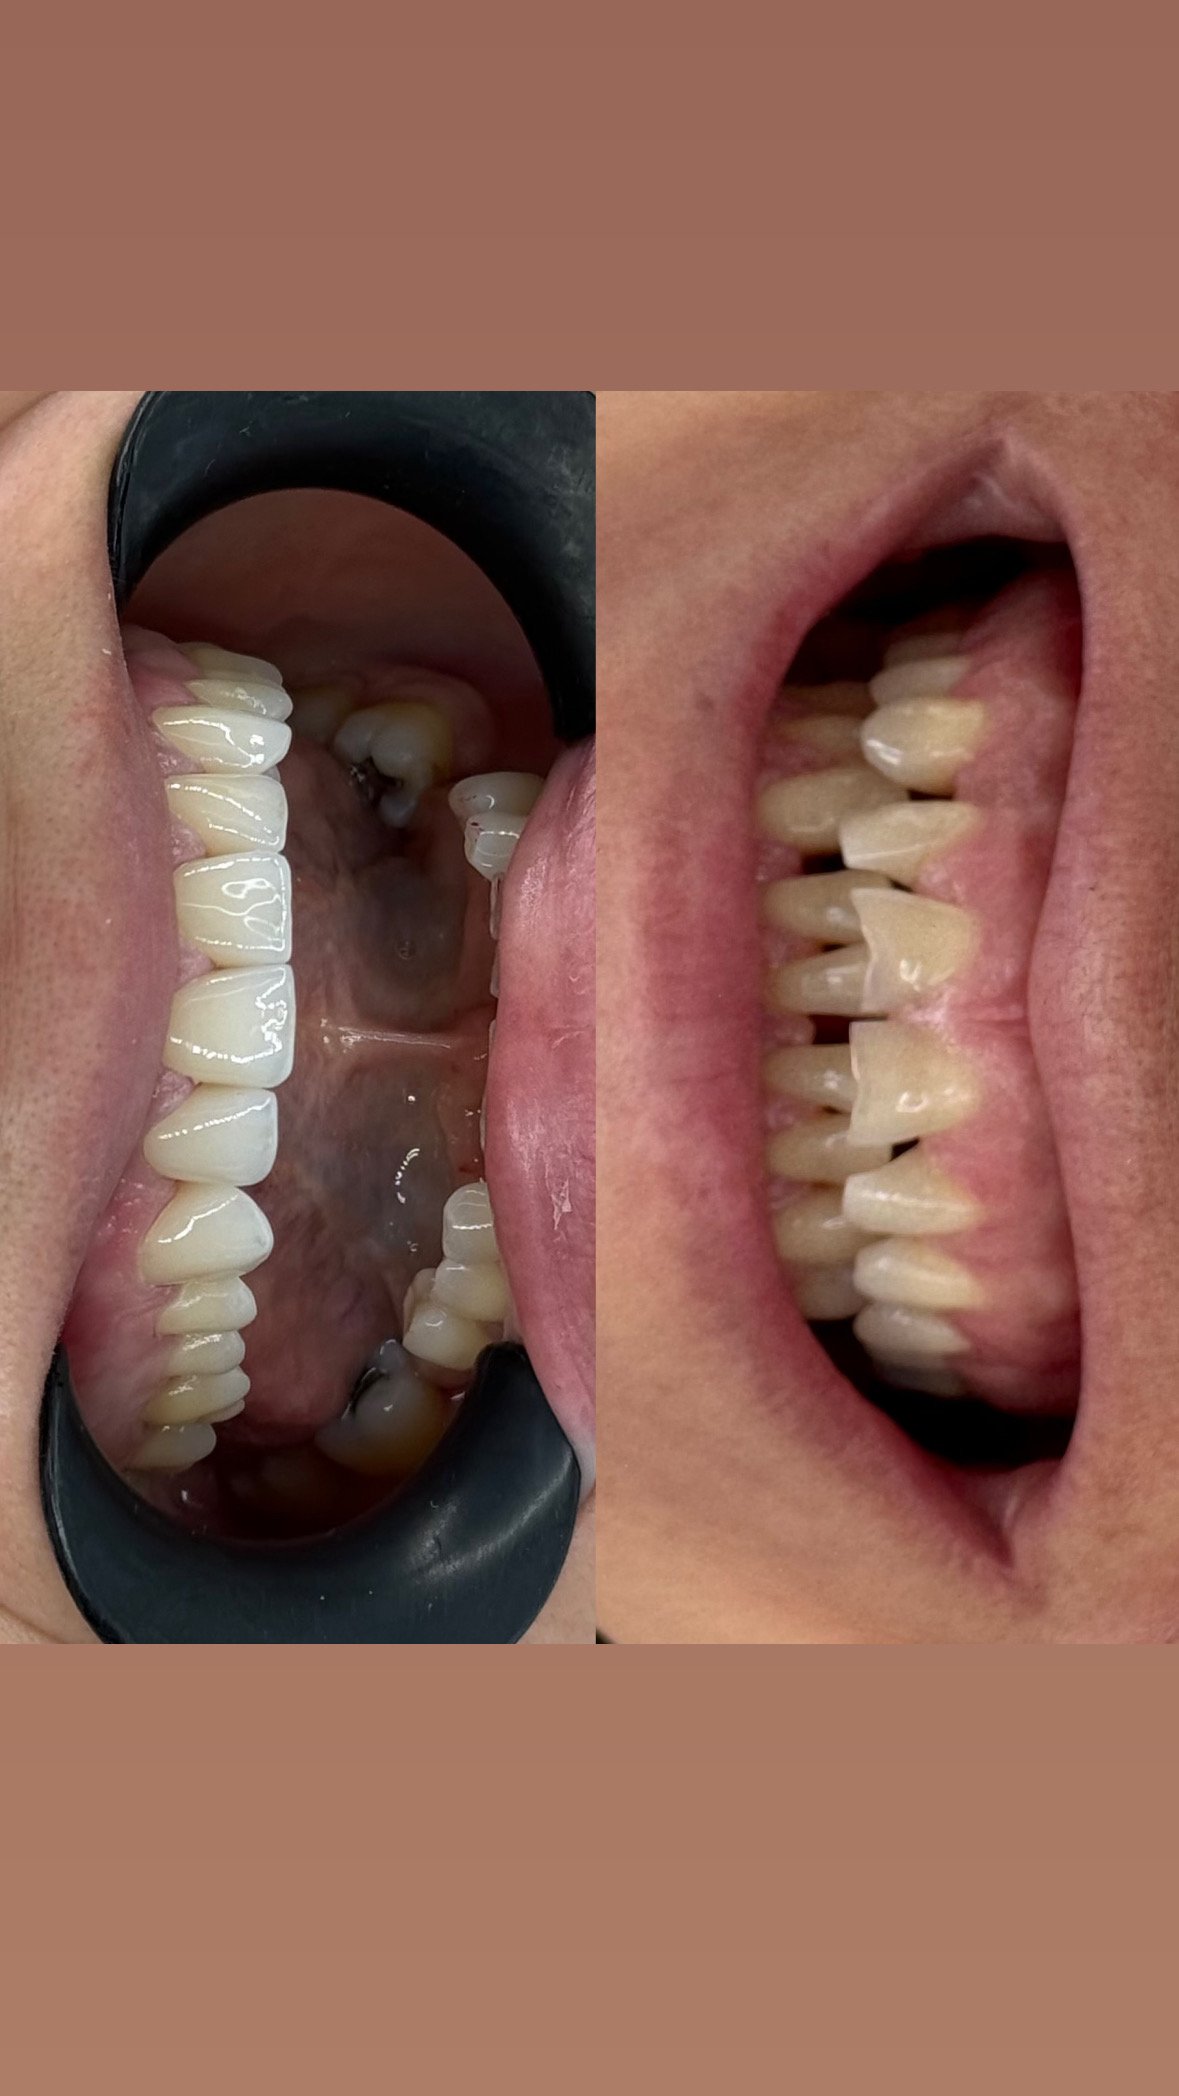

Screenshot